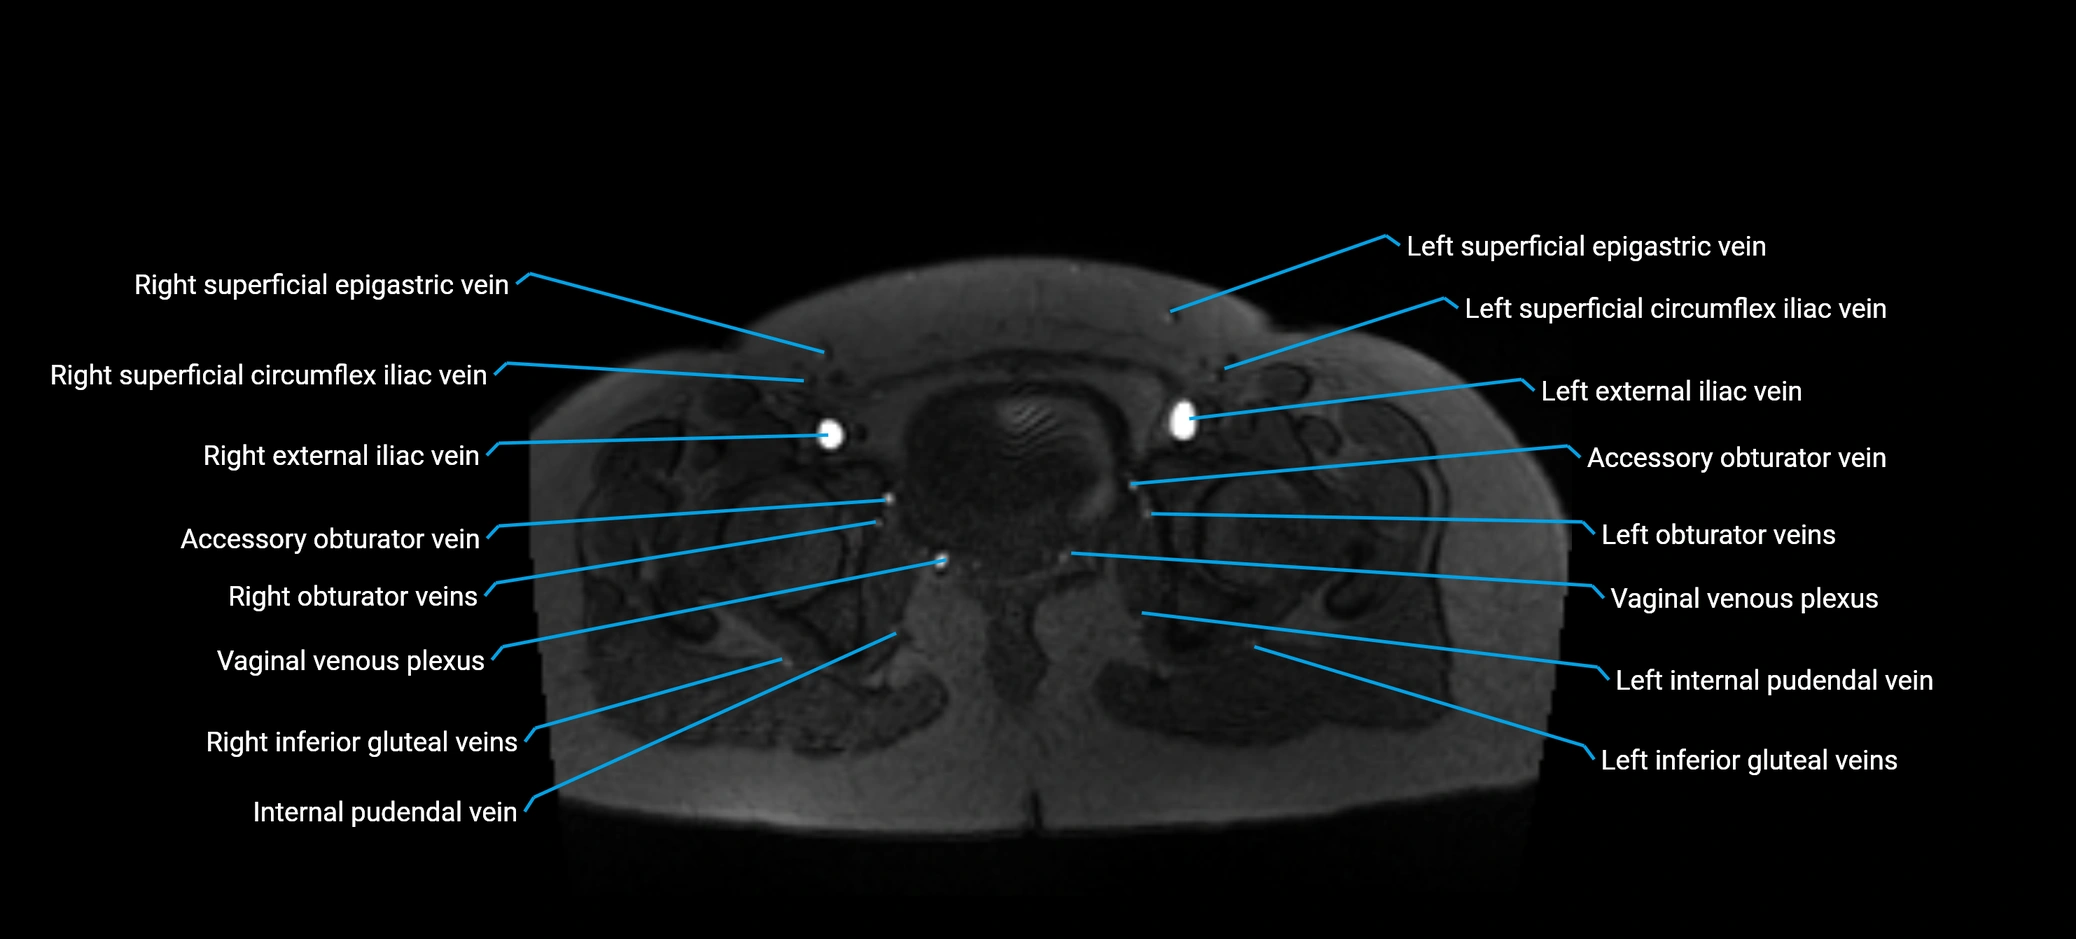

MRI image

image